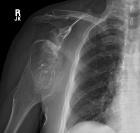

68 yo male with complaints of right shoulder pain with repetitive activities and modified with rest. History of multiple orthopaedic surgeries in the past. He denies history of trauma or constitutional symptoms.

PE: Elderly male in good overall health. Short stature. Palpable mass in posterior right shoulder. Nontender w/o edema or overlying skin changes. Limited ROM in all dimensions. NVI w/o LAN.